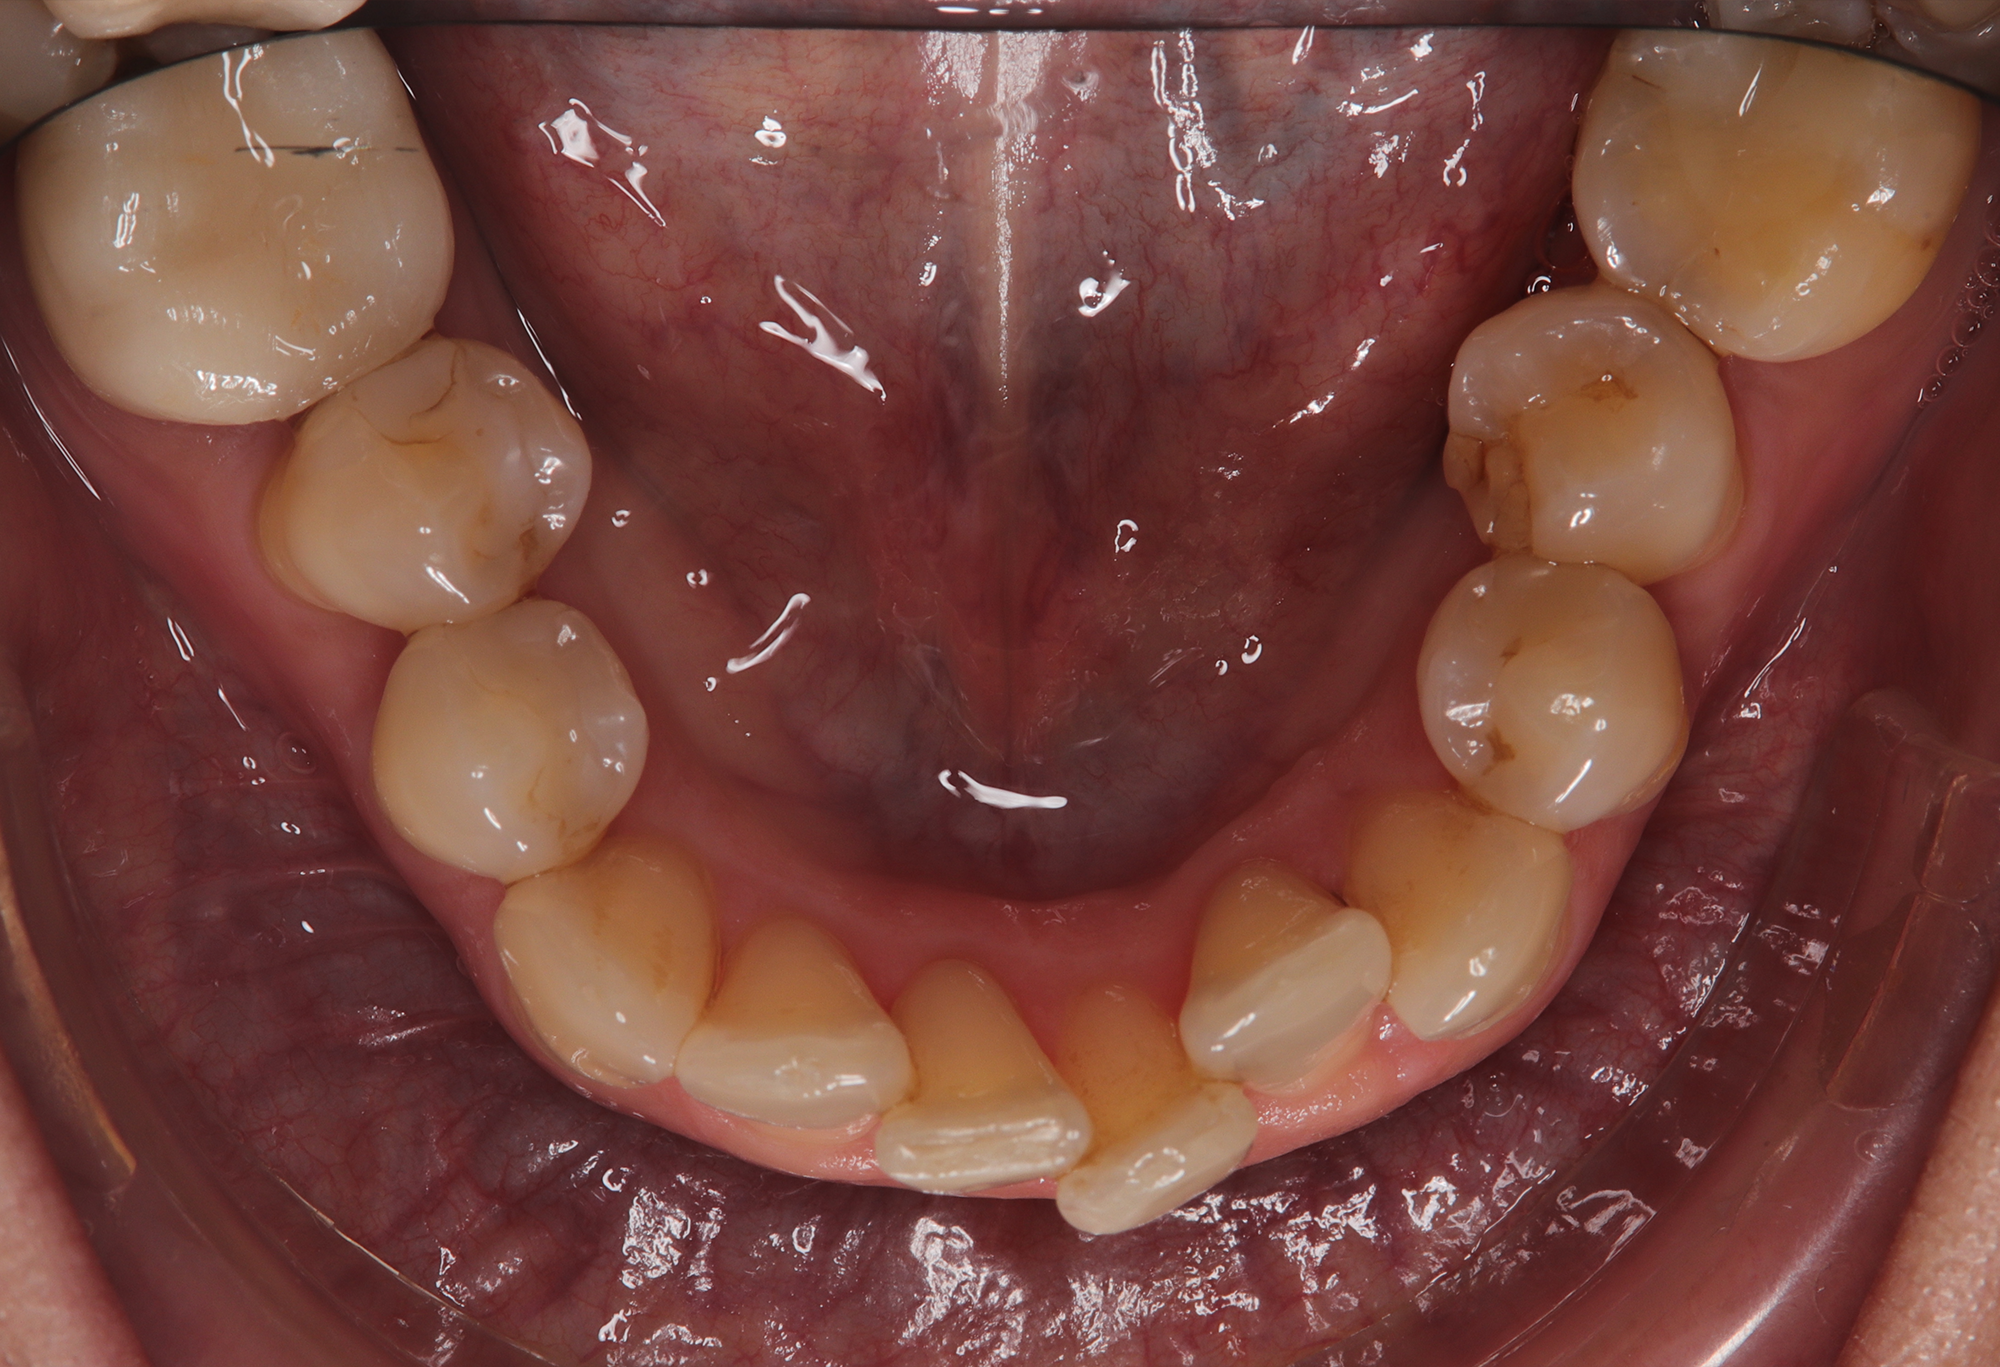

To refine the results and enhance aesthetics, a second phase incorporating an additional 17 aligners was introduced. During this refinement stage, careful IPR in the lower arch helped harmonize the midline and achieve a balanced occlusion. Once satisfactory alignment was reached, provisional composite restorations were placed on the upper lateral incisors to aesthetically close any interproximal gaps.

Treatment results

At the conclusion of the treatment, the patient achieved excellent dental alignment and a stable occlusal relationship, particularly in the anterior region. Radiographs and clinical assessments confirmed that there was no further bone loss and that previous improvements were maintained. The aesthetic enhancement from the composite restorations further contributed to the overall success of the treatment.